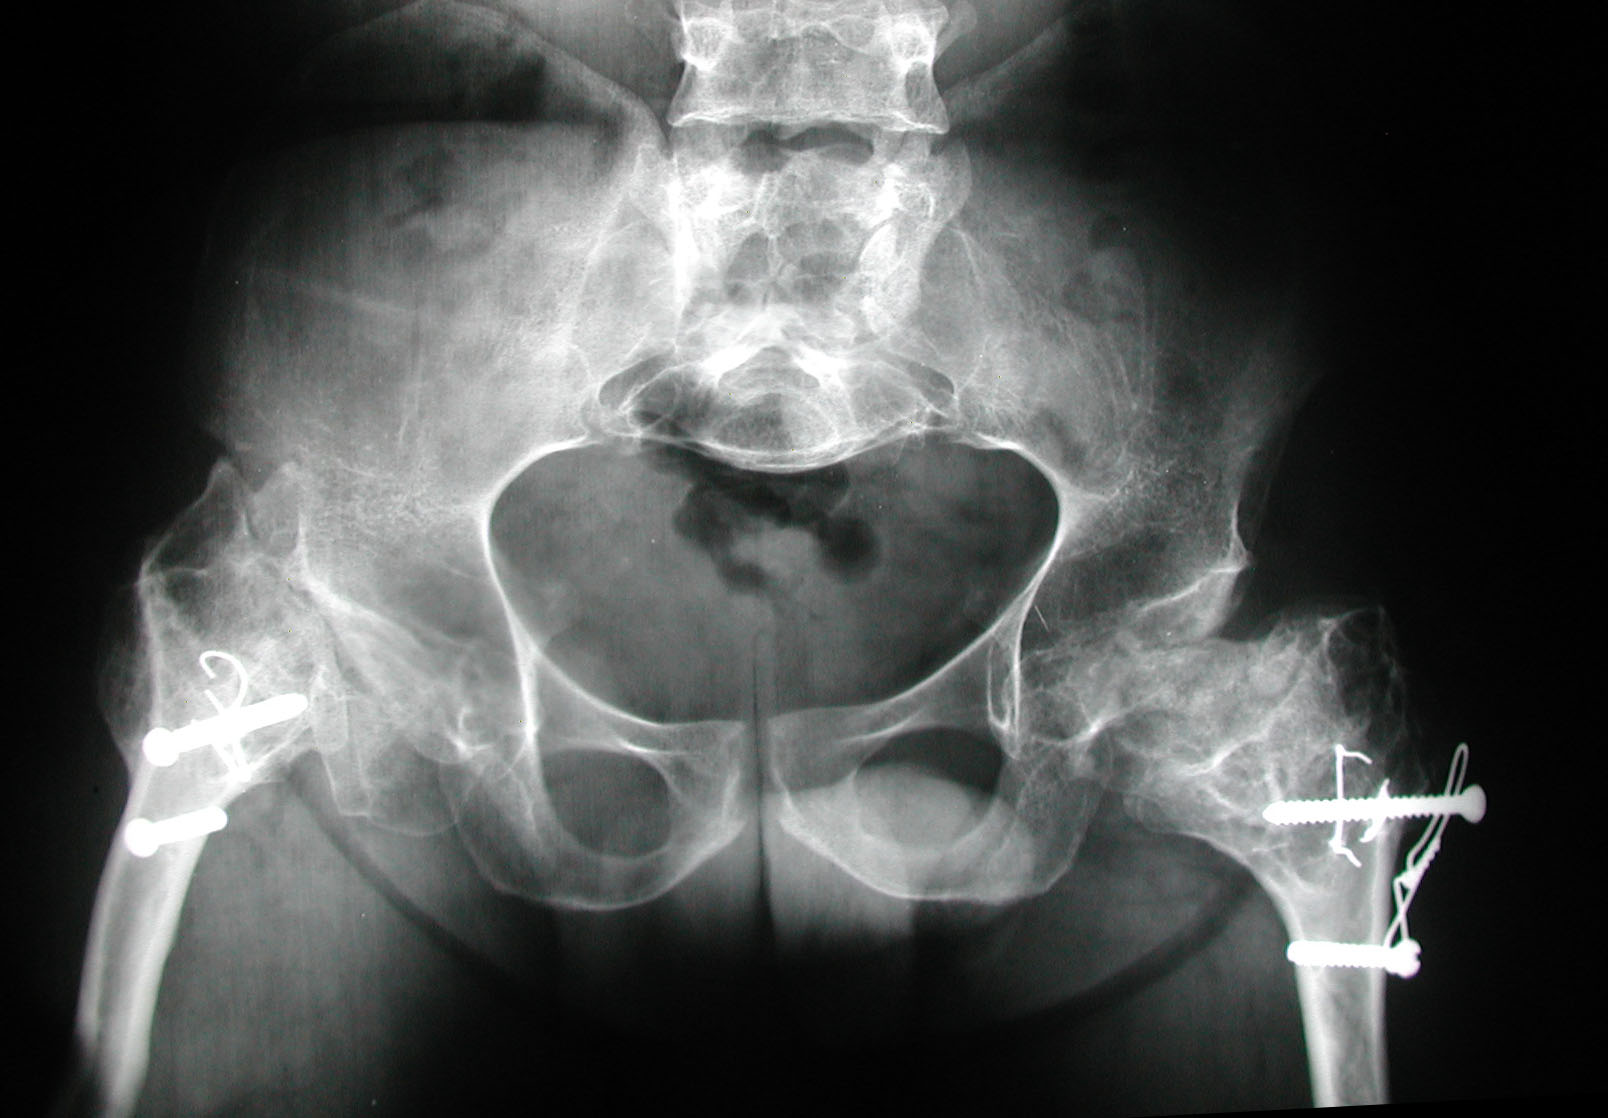

Seudoacondroplasia. [Pseudoachondroplasia]

7. Sekundiak TD. Total hip arthroplasty in patients with dwarfism. Orthopedics 2005;28(9):1075-8.

8. Huo MH, Salvati EA, Liberman JR, Burstein AH, Wilson PD Jr. Custom-designed femoral prostheses in total hip arthroplasty

done with cement for severe dysplasia of the hip. J Bone Joint Surg Am 1993;75:1497-1504.

9. Osagie L, Figgie M, Bostrom M. Custom total hip arthroplasty in skeletal dysplasia. International Orthopedic 2012;36:527-1.

10. Chiavetta JB, Parvizi J, Shaughnessy WJ, Cabanela ME. Total hip arthroplasty in patients with dwarfism. J Bone Joint Surg

Am 2004;86:298-303.

11. Ain MC, Andres BM, Somel DS, Fishkin Z, Frassica FJ. Total hip arthroplasty in skeletal dysplasias. Patients selection,

preoperative planning, and operative techniques. J Arthroplasty 2004;19(1):1-7.